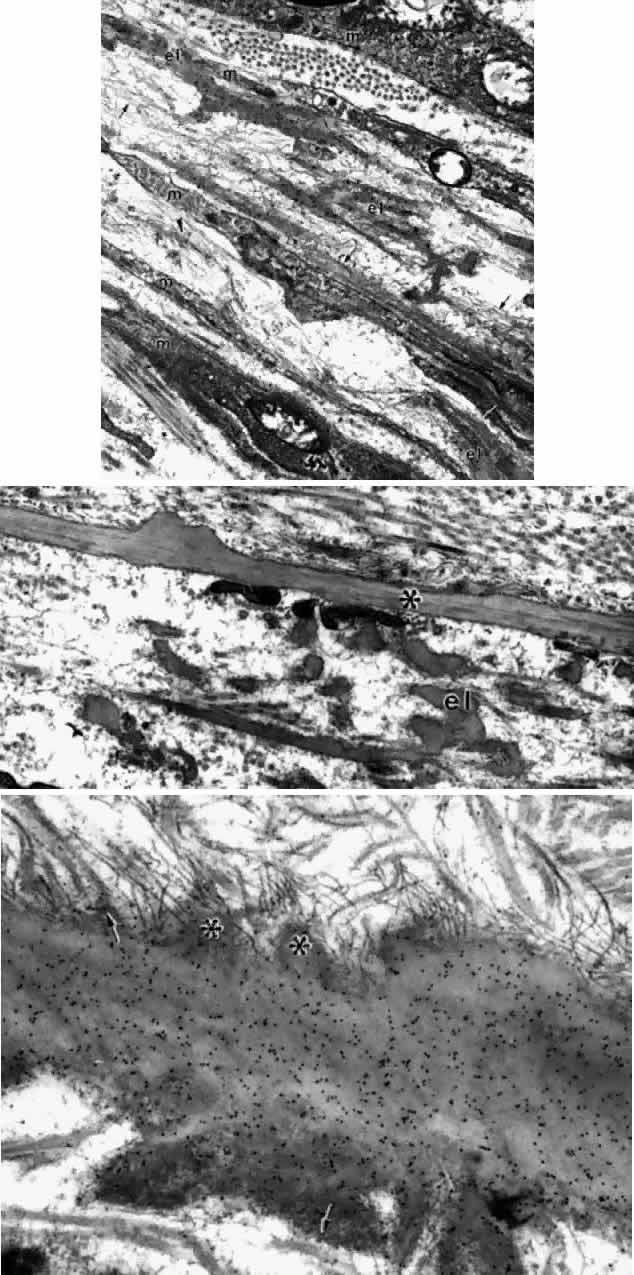

Elastic fibers are composed of two major components, the 10- to 12-nm elastic system microfibrilswith 12-nm microperiodicity, and the homogeneous electron-lucent core of elastin. The elastic microfibril is tubular in cross section, beaded on rotary shadowing, and belongs to the same family as the zonular fibril.31,32 When aggregated together without elastin, these microfibrils are called oxytalan fibers (Fig. 32A). Elastin molecules are laid down on this microfibrillar template during elastogenesis (Fig. 32B), completely obscuring the microfibrillar substructure in mature elastic fibers (Fig. 32C). Nonelasticized oxytalan fibers are ubiquitous throughout most connective tissues and are plentiful throughout the ciliary body. They serve as connecting or anchoring fibers between basement membranes of epithelia, vessels, muscle bundles, and nerves, and link together different portions of the elastic fiber system in the ciliary body33 (see Figs. 27, 29, 33) as in other tissues.34 Incompletely elasticized fibers with many remaining microfibrils (elaunin fibers) are also seen (Fig. 32D).32 Besides the subepithelial elastica continuous with Bruch's membrane, mature elastic fibers are not frequent in the ciliary body except at the muscular insertions (see next section).

Fig. 32. Elastic fiber system. A. Bundles of elastic microfibrils (oxytalan) in zonule, showing 12-nm microperiodicity (arrow). (X 51,900) B. Developing elastic fiber with cords of amorphous electron-lucent elastin being laid down on the microfibrillar template. Orbit of 14-month-old child. Note same 12-nm microperiodicity (arrow). (X 51,700) C. Large mature elastic fiber (Bruch's elastica, tangential cut) at site of two branches (arrowheads). Scanty attachment microfibrils peripherally. Gold-labeled with elastin antibody. (X 51,700) D. Predominantly microfibrillar (arrows) elastic fibers (elaunin type) in trabeculum. Elastin-antibody binding to central white elastin cords (arrowhead) in 2-month-old infant. (X 51,700)

THE ANTERIOR INSERTION OF THE CILIARY MUSCLE

The possibility that the ciliary muscle fibers insert anteriorly in the region of the scleral spur via “elastic tendons” was proposed by Rohen several decades ago.37 He and his colleagues have made continual progress in understanding the anterior muscle insertion and more recently the posterior insertion, adding a new hypothesis about the cause of accommodative loss with aging. Three types of anterior tendons are described.56 One attaches the tapering longitudinal muscle bundles to the anterior sclera and scleral spur, and the second anchors in the trabecular meshwork. Both consist of fibers described as elastic-like, showing extensive connections to the elastic fibers of the scleral spur and the juxtacanalicular elastic system (“cribriform plexus”56) as well as to the trabecular meshwork (Fig. 40). The fibers were called elastic-like because they do not resemble normal elastic fibers and are not completely digested by elastase. Ultrastructurally in the infant they contain a relatively small amount of elastin in unfused cords with large numbers of elastic system microfibrils, like an elaunin fiber (see Fig. 32D). However, the microfibrils become obscured by 50-nm granular banded “sheath” material by the second decade, and later an outer layer of 100-nm banded material. This coating is reported to contain collagen VI and chondroitin sulfate.57 The banded material increases markedly with age and in chronic open-angle glaucoma. The origin of the third type of tendons is less clear, but they are broad collagenous bands that cross the meshwork to insert in the peripheral corneal stroma.

Ultrastructurally, the anterior ends of the ciliary muscle fibers taper toward their attachment at the scleral spur and the trabecular meshwork, associated with a plethora of elastic microfibrils and small banded elastic fibers running parallel to them (Fig. 41). In areas of elastic fiber contact, there are dense focal bands on the muscle cell membrane to which intracellular actin filaments are attached. This kind of contact is similar to elastic tendons connecting the arrector pili smooth muscle fibers to hair follicles, where the tendons are composed of oxytalan and elaunin fibers.59 However, there has rarely been reference to the unique 50-nm banding on these nonocular elastic fibers. Accompanying collagen fibers running along the ciliary muscle in the same direction may be part of the tendon. With aging, the tendons are enveloped by extensive fibrogranular elastotic debris besides banded material (Fig. 42).